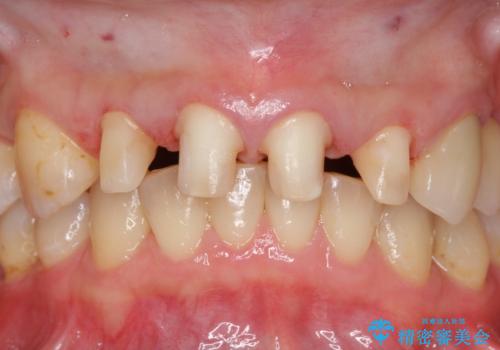

前歯の虫歯 つぎはぎの歯をセラミックに

下の前歯との距離(クリアランス)が大きくは取れなかったため、ジルコニアクラウンではなくe-maxクラウンにしました。

また、歯ぎしりでセラミックがかけるのを防ぐために、就寝時にはナイトガードを装着してもらっています。